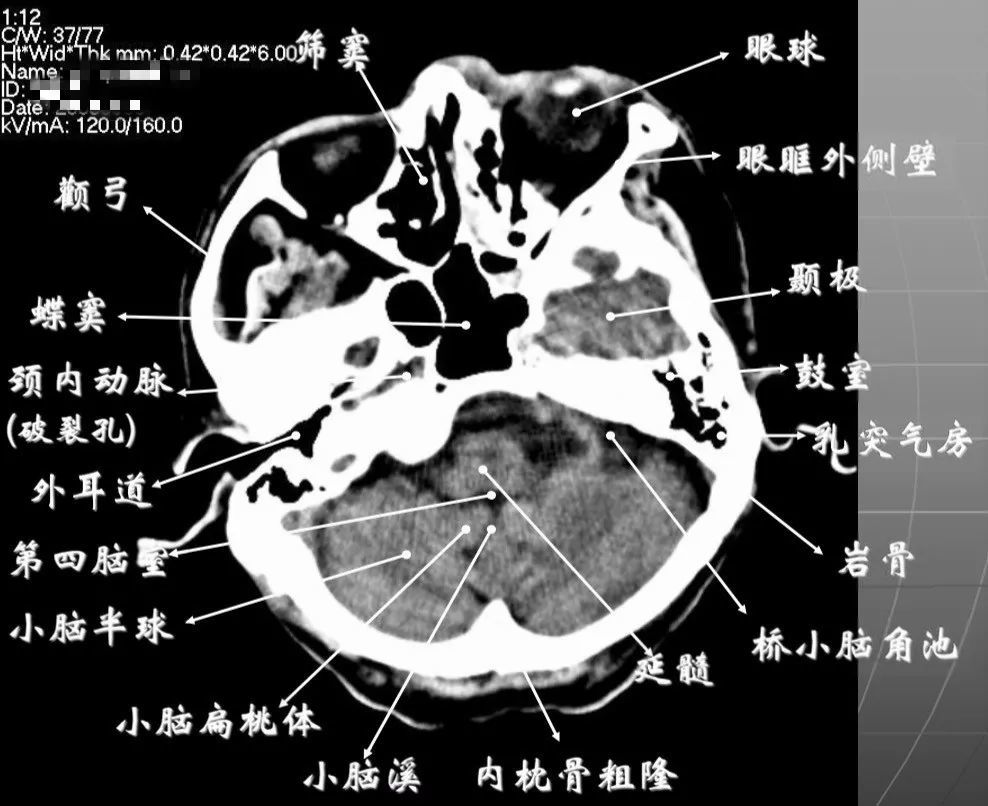

详细标注版——颅脑ct正常解剖图谱_中央_小脑_纤维

图片尺寸1080x626